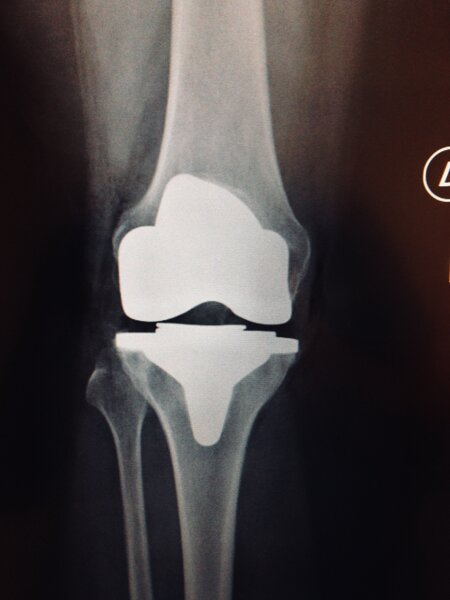

La protesi di ginocchio consiste in un rivestimento completo o parziale dell'articolazione, quindi ricoprendo sia la superficie articolare della tibia che quella del femore. A discrezione del chirurgo ed in base al caso specifico si può rivestire anche la rotula. Volendo semplificare la procedura di impianto di una protesi di ginocchio si possono individuare alcuni passaggi dell'intervento:- preparazione delle superfici ( si asportano i residui di cartilagine, esponendo l'osso sub-condrale in modo da avere una base di appoggio uniforme per la protesi )

-impianto delle componenti metalliche ( si impiantano due componenti metalliche articolari una per il femore e l'altra per la tibia, che costituiranno la nuova articolazione )

-posizionamento dell'inserto ( tra le due componenti metalliche del femore e della tibia viene posizionato un inserto in polietilene cioè una plastica ad alto peso molecolare, per curare la superficie di scorrimento ed ammortizzare i carichi, per sostituire la funzione dei menischi, l'inserto può essere fisso oppure mobile attorno ad un perno centrale )

-impianto della rotula ( si può decidere o meno in base al caso specifico se impiantare la protesi della rotula a seconda delle condizioni della cartilagine e della sintomatologia del paziente )

Intervento sicuro, elimina il dolore e corregge eventuali deformità della gamba. Dopo questo intervento potrai riprendere la tua vita di sempre e le normali attività senza dolore.